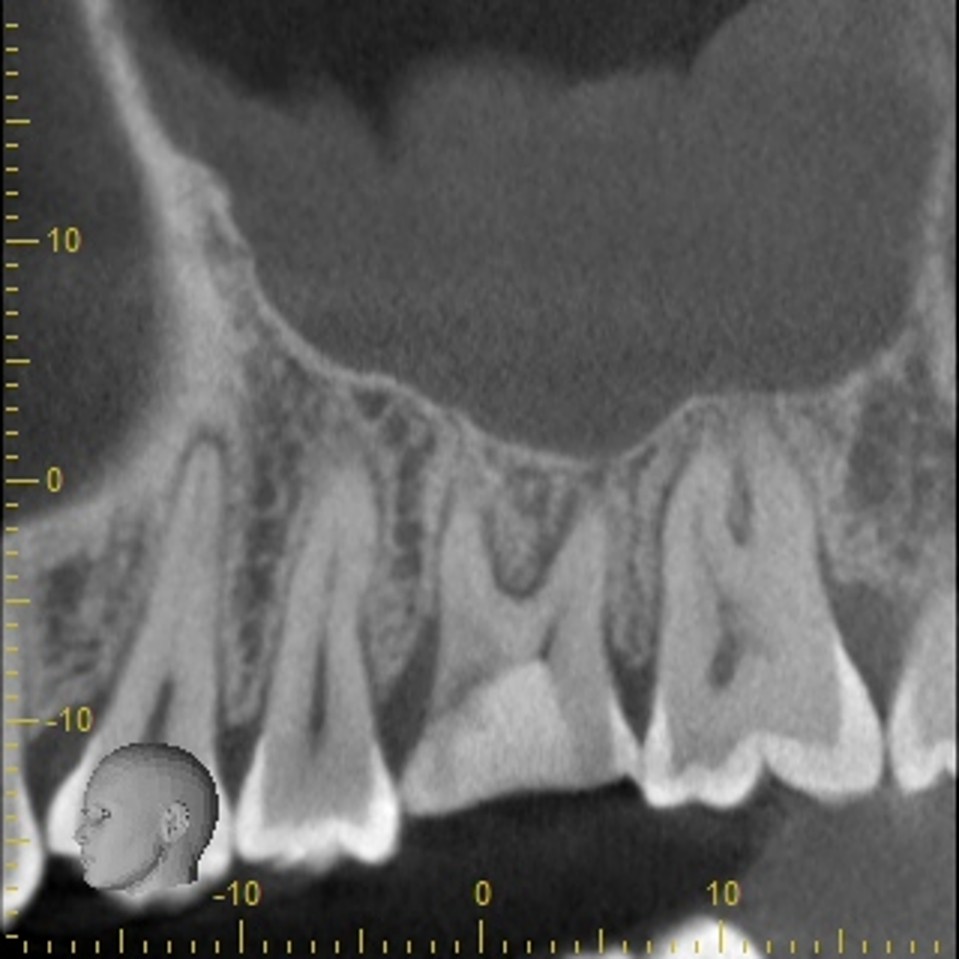

上の奥歯は上顎洞までの距離が短くインプラントが難しいことも多いのですが、即時埋入用に開発されたインプラントを使えば抜歯と同時にインプラント埋め込みまで行うことができると判断しました。

4ヵ月で最終的なセラミック冠を装着しています。

CTスキャンで確認してみても上顎洞炎もきれいに治っていることが分かります。